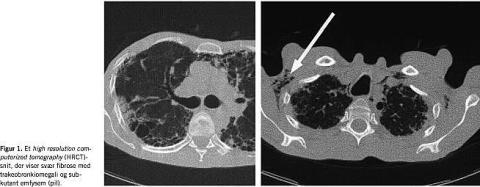

Under patientens indlæggelse i februar 2003 på et andet sygehus gav dyrkninger og undersøgelser for typisk bakteriel og atypisk pneumoni alle negativt resultat. Patienten blev udskrevet afebril. Forud for indlæggelsen i marts 2003 havde han haft et vægttab på ca. 15 kg. Der var hørlig krepitation basalt ved auskultation, trommestikfingre, men ingen hypermobilitet. C-reaktivt protein var på 12. Der var ikke påviselige præcipiterende antistoffer for undulat. En thoraxrøntgen viste udtalt fibrose, højresidig kappepneumothorax og subkutan emfysem. Et thoraxrøntgen fra februar 2003 viste lille venstresidig kappepneumothorax og svær fibrose. En high resolution computerized tomography (HRCT) af thorax (Figur 1 ) viste trakeobronkiomegali, fibrose (bikagetegning), bronkiektaser, emfysem og subkutant emfysem, men ingen sikre områder med matglastegning.

Den idiopatiske, fibroserende alveolitis i form af usual interstitiel pneumonia (UIP) er den mest sandsynlige diagnose, idet systemsygdom, erhvervspåvirkning og medikamenter kan udelukkes som årsagen [3]. Diagnosen allergisk alveolit blev overvejet pga. patientens kontakt med undulater. Trakeobronkiomegali [4], der er karakteriseret ved mangelfuld brusk i det trakeobronkiale træ og relateret til andre anomalier og systemsygdom som f.eks. Ehlers-Danlos syndrom, er også tidligere beskrevet som komplikation til diffus lungefibrose og hos unge med obstruktiv lungesygdom [4].